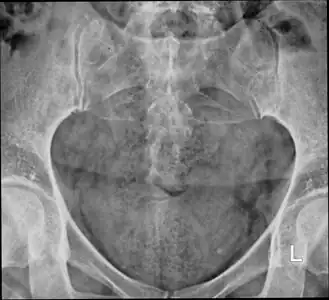

X-ray

Lateral radiograph showing a fracture of the coccyx, as well as a lower lumbar fracture